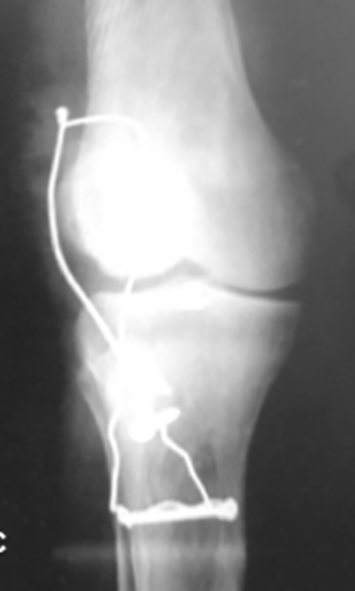

En la última evaluación clínica del primer caso a los 2 años del procedimiento quirúrgico se encontraron rangos de movilidad completos, fuerza 4/5 en la extremidad derecha y 5/5 en la extremidad izquierda, moderada atrofia muscular y total integración de injerto TC al mecanismo extensor de rodilla derecha (Figura 3). El segundo paciente a los 3 meses de la cirugía presentaba un rango de movilidad completo, fuerza 4/5, de la extremidad derecha y marcha sin soporte. Este caso lleva 10 años de evolución sin detrimento de su función o complicaciones.